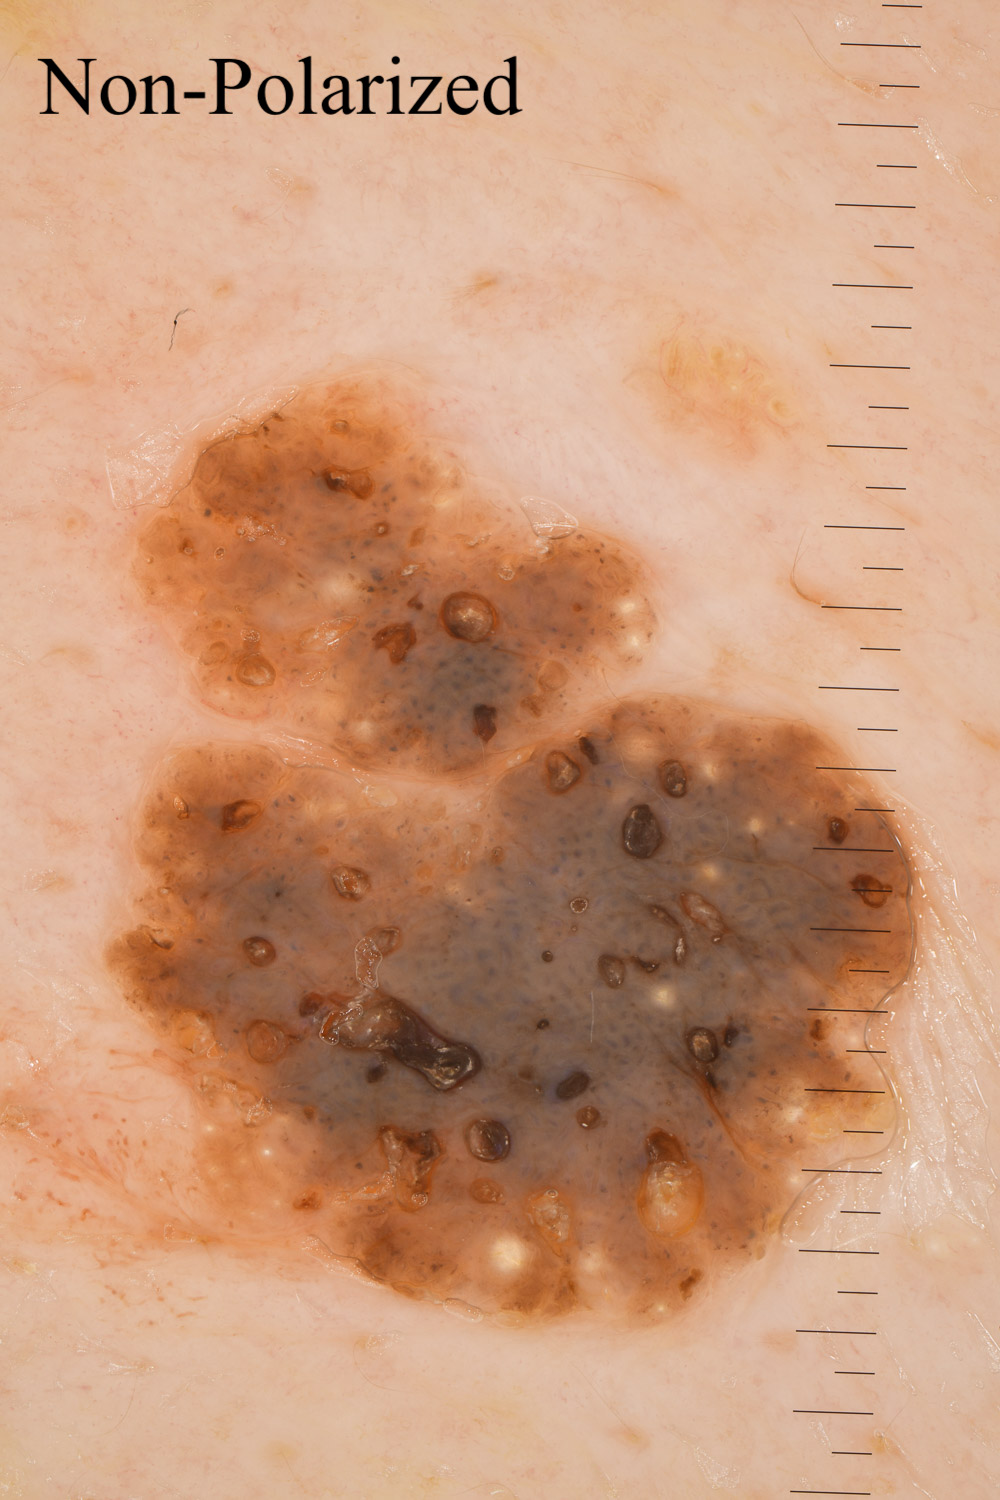

Case: 10